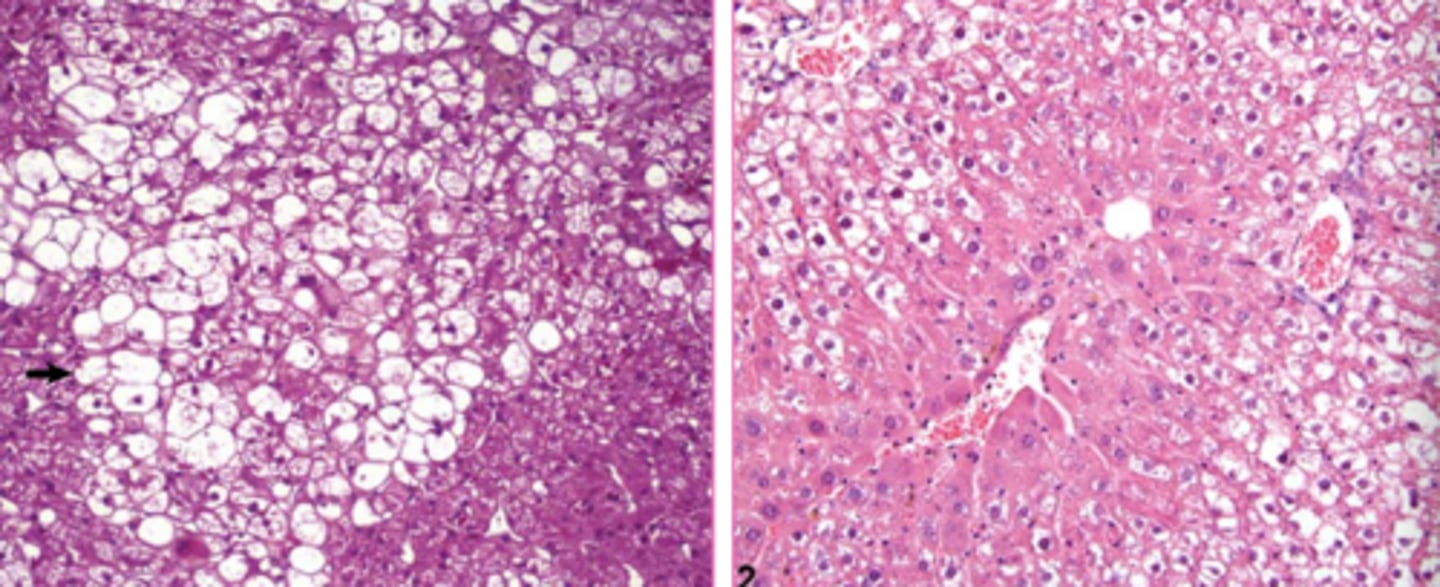

macrovesicular lipidosis

Which type of lipidosis is this describing?

Large, clear, sharply defined vacuoles that are larger than the nucleus, distend the

cytoplasm, and displace the nucleus to the periphery of the cell

macrovesicular hepatic lipidosis

yellow arrow?

<p>yellow arrow?</p>

microvesicular hepatic lipidosis

blue arrow?

<p>blue arrow?</p>